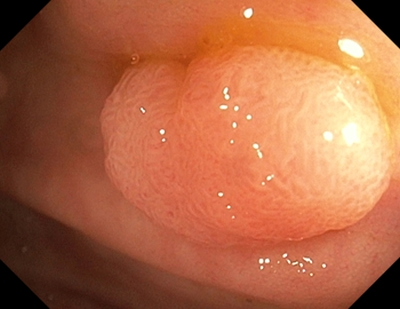

1 тип — характерний для гіперпластичного поліпа

Судини: світліші або схожі на навколишні

Поверхня: круговий візерунок з дрібними крапками — візерунок із темнішою ділянкою в центрі, оточений світлішою слизовою оболонкою